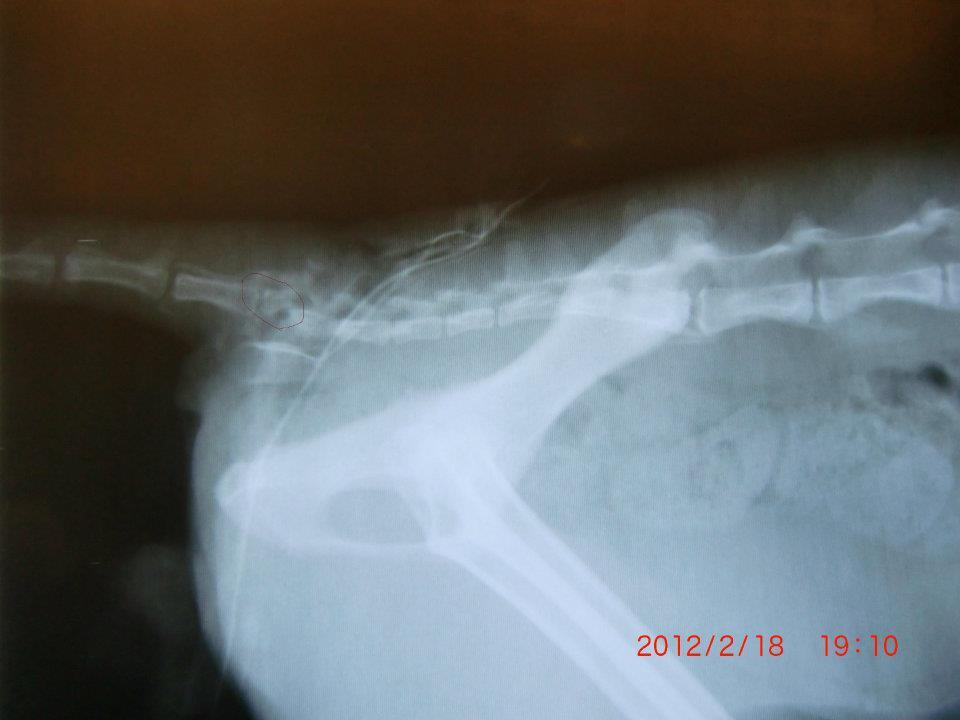

主題: 中壢尾椎傷貓 申請者姓名: Vivi Sung 花色: 申請日期: 2012-02-18 21:35:03 申請者部落格: 申請者臉書網址: http://www.facebook.com/media/set/?set=a.343873802302736.78011.100000403568717&type=1 所在縣市/合作醫院: 桃園縣/思邁爾動物醫院 治療費用: 9000元 需求人數: 9人 已結案 (2012-05-29 19:58:11) 報名人員: Lexie Liu(已付款)、Meg Chen(已付款)、Green D Chen(已付款)、Cay Way(已付款)、Kirsty Lin(已付款)、miohsieh(已付款)、鄭小V(已付款)、余小易(已付款)、Fiona WU、 候補人員: su(已付款)、Shirley、 動物病情說明: 由中壢游先生救援..

第五結尾椎受傷嚴重.其中致命的傷來自一個看似受傷的小洞,卻已經咬到尾椎!傷口內全是膿.將預計一周清創,結紮等醫療